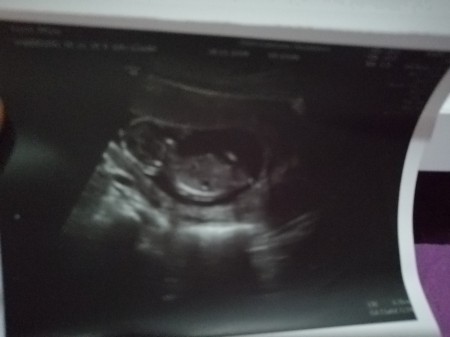

Cinsşyette tahmini

cinsiyet tahminiiii

Kesen yuvarlak canım başı da sağda sanki kız :)

buna nediyosunuz kızlar :)

Kesenin ya da bebeğin sağ ya da solda olmasını nasıl anlıyorsunuz kızlar? Resimde göründüğü gibi mi yoksa tam tersi mi oluyor sağ sol taraf nasıl oluyor